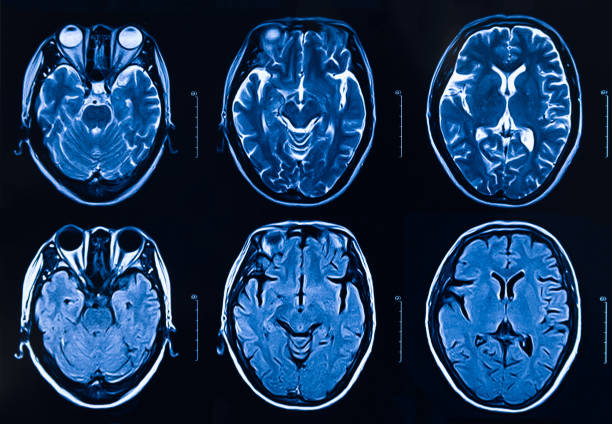

本研究納入2018年1月1日至2020年10月31日發(fā)病168小時(shí)內(nèi)發(fā)生急性ICH的患者。間充質(zhì)干細(xì)胞被靜脈注射給9名患者(5名女性,4名男性),平均年齡(范圍)為61(36-84)歲。表1總結(jié)了人口統(tǒng)計(jì)學(xué)和臨床??特征 。出于描述目的,患者按照入組順序獲得編號(hào),并連續(xù)分配到三組中的一組,每組三人。根據(jù)模型 2 分割,ICH體積范圍為0.1至54.9mL(平均ICH體積為23.5mL)。5例ICH累及局部腦葉,其余則位于基底節(jié)或外囊深處。在三名患者中,ICH位于丘腦(圖1),在一名患者中,血腫位于多個(gè)腦結(jié)構(gòu)(即尾狀核、殼核和蒼白球)。平均而言,MSC在ICH后3天進(jìn)行注射。